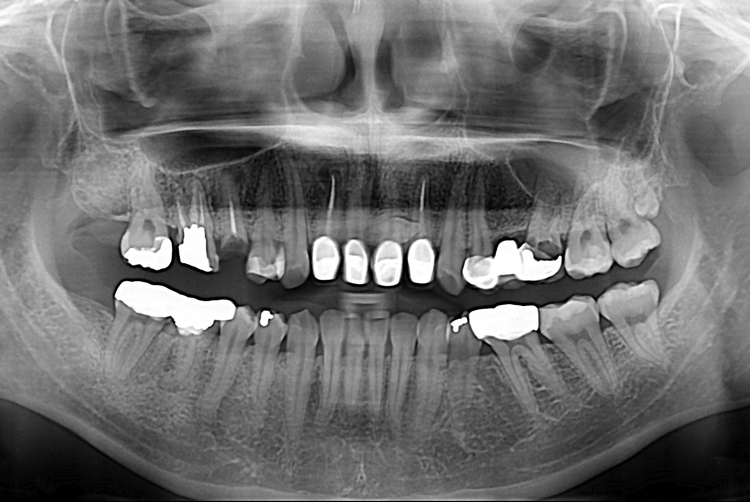

[임플란트] 어금니 임플란트

치료전 : 2018-08-27

세종치과는 많은 환자와 다양한 케이스를 바탕으로

항상 편안한 임플란트 수술을 제공하고자 노력하고,

오래동안 튼튼히 쓸 수 있는 임플란트 수술을 가장 큰 목표로 삼고 있습니다.